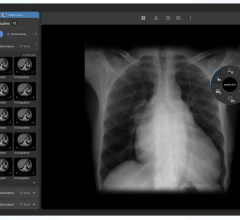

Candelis Inc. will showcase its recently FDA cleared ImageGrid Mammography Web Viewer and ImageGrid Radiology Web Viewer, which are now part of the ImageGrid RIS/PACS Appliance technology suite, at SIIM 2008.

The ImageGrid Mammography Web Viewer and Radiology Web Viewer are diagnostic tools aiming for timely access to medical imaging studies from anywhere and at any time to improve patient care. Both viewing applications are highly scalable and designed to

accommodate multiple concurrent users without the need to invest in additional servers, said the company. As a multi-modality visualization solution, the viewers allow radiologists to view all relevant prior studies from one workstation.

For hospitals with specialty imaging departments, the ImageGrid RIS/PACS Appliance provides immediate access and diagnostic viewing capabilities from any workstation on the network. As a thin-client application, the ImageGrid Web Viewers do not require installation of costly software on every workstation on the network or at a physician’s remote workstation.